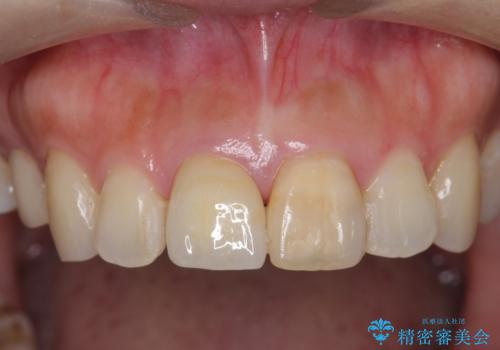

- 歯の神経を除去したのちの、変色の改善を希望され来院されました。

再度根管治療を行ったのちの、オールセラミッククラン治療を計画します。